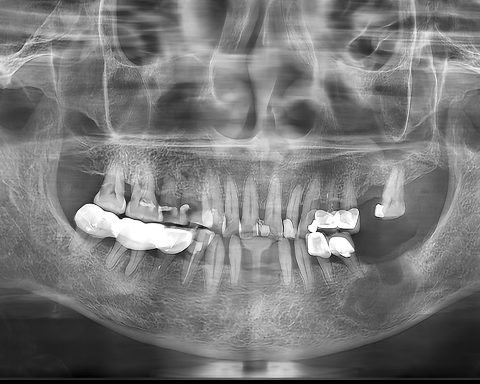

水母网1月12日讯(通讯员 王茜玮 李姝慧)原本李女士只是想到烟台市口腔医院体验一下市民健康保赠送的免费洗牙服务,顺便做个口腔检查,结果洗完牙后被医生叫住了。“您的X光片显示下颌骨有个区域需要特别关注,”医生指着影像说道,“这里有个阴影,可能需要做进一步的检查。”

李女士的CBCT结果证实了医生的猜测。医生指着屏幕上清晰可见的椭圆形区域解释道:“您看,这是一个囊性病变,大约有核桃大小。它紧挨着几颗重要的牙齿根部。目前看来,这些牙齿的牙根都还保持完整,没有受到侵蚀。”

三个月后复查时,影像对比显示出了令人欣喜的变化——原先占据相当空间的囊肿区域已经显著缩小,周围的骨质也开始呈现出健康的修复迹象。“更让我放心的是,整个治疗过程都很温和,正常牙齿功能完全没受影响。”李女士说道,病理结果也出来了,就是根尖囊肿,医生说以后只要定期复查,检测恢复情况就可以了。”